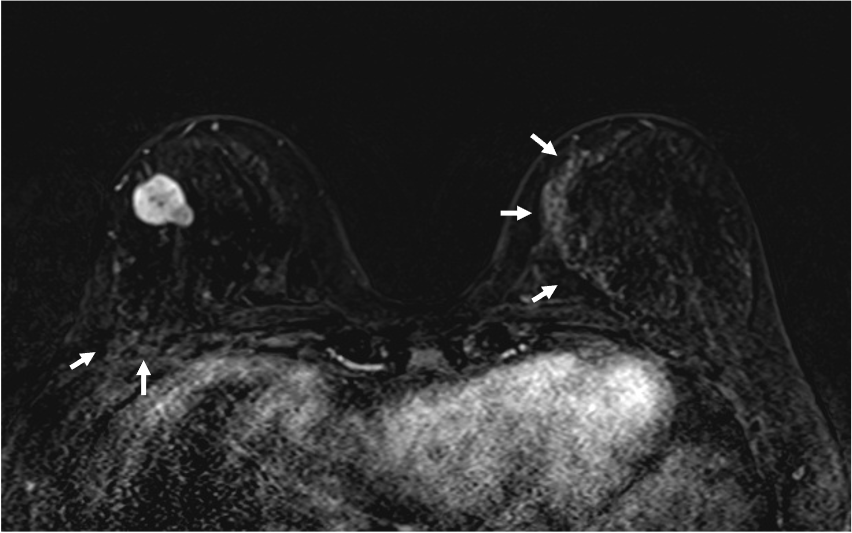

早期相で、乳腺の辺縁にBPE(矢印)を認めるが、その範囲は広くなくmildと判定する。乳癌の病変は、早期相から急速に造影され、遅延相でwash outがみられる。BPEは、遅延相で拡大し増強している。

6. 造影後高分解能画像

乳癌の病変の形態は、不整形で、rim 状の造影域を認める。高分解能画像では形態的な性状を鮮明に観察できる。